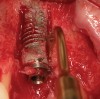

Figure 14  (Case 2) Failed implant at surgical exposure.

Figure 14

Figure 15  (Case 2) Defect after implant removal.

Figure 15

A 53-year-old woman presented with a failing implant in the No. 7 site (Figure 12 and Figure 13). Her desire was to eliminate infection and preserve esthetics. A team effort between the periodontist and restorative dentist to advocate for additional restorative dentistry as well as manage the patient’s expectation of time required was essential. In addition, the patient needed to have realistic expectations of a compromised outcome. Both the restorative dentist and the periodontist informed the patient about the difficulty of achieving this with acceptable esthetic results. Mutual emotional and technical support was required to successfully complete this case, from initial grafting of the defect to placement of anterior restorations (Figure 14 through Figure 23).